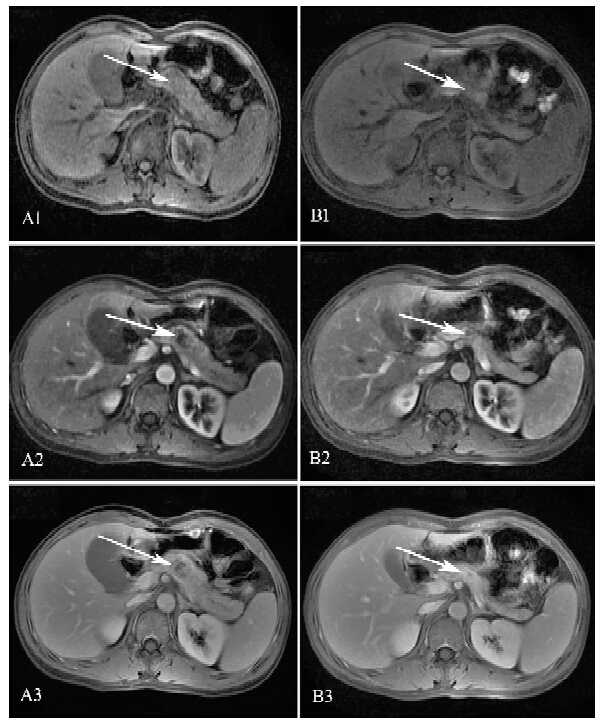

经过禁食3 d,静脉予抑酸、抑酶及抗感染等治疗后,患者上腹痛明显缓解,血清淀粉酶下降至345 U/L。但体温反复,最高39.2℃。完善上腹部MRI平扫+增强提示胰体部可见一囊实性异常信号影,大小约为26 mm×23 mm,肝S6段见一类圆形稍长T1稍长T2信号影,大小约为21 mm×14 mm。影像学诊断考虑胰体部囊实性病变为恶性肿瘤,并肝S6段转移可能(图 1)。因此我们认为是肿瘤侵袭所致的急性胰腺炎。行胰腺肿块超声引导的经皮细针抽吸(FNA)活检。 病理提示部分细胞中等大、圆形,有腺样结构趋势,部分细胞有变性,核大深染,轮廓不清,有异型性,考虑为恶性肿瘤细胞,倾向于NK/T细胞淋巴瘤,但不能完全排除胰腺原发肿瘤(图 2)。但因取材不足,无法完善免疫组织化学检测。

图 1 结外鼻型NK/T细胞淋巴瘤患者腹部MRI扫描 MRI图像在静脉期的对比度增强;A:平扫时胰体部可见一囊实性异常信号影,大小约为26 mm×23 mm,胰腺尾部一贯轻度不均匀扩张(A1);动脉期(A2)病灶边界信号增强,延迟动脉期(A3)时信号进一步增强;B:在2个疗程的化学治疗后,胰腺病灶缩小至13.2 mm×11.7 mm |

患者最终被诊断为结外鼻型NK/T细胞淋巴瘤,侵袭胰腺与肝脏。患者接受了8个疗程的静脉化学治疗及2次鼻咽部的放射治疗(约60 Gy/30f)。化学治疗包括EPOCH方案(依托泊苷、阿霉素、环磷酰胺、长春新碱、泼尼松)2个疗程,然后EPOCH+培门冬酶2个疗程,然后EPOCH+左旋门冬酰胺酶及EPOCH+左旋门冬酰胺酶+博来霉素各1个疗程,最后为CHOP+博来霉素2个疗程。此外,行腰椎穿刺及鞘内注射甲氨蝶呤预防中枢神经系统淋巴瘤。患者胰酶水平在第1程化学治疗后恢复正常。第2程、第4程化学治疗后疗效评估为部分缓解。 第6程化学治疗后胰腺病灶消失,肝脏中的病灶几乎消失。鼻咽部肿物在第2程化学治疗后缩小至11.5 mm×3 mm(图 3),在第8程化学治疗后几乎消失。化学治疗结束9个月后患者因发热3 d来我院就诊,复查鼻咽部CT平扫+增强提示左颌下淋巴结稍大,鼻咽部及鼻腔、副鼻腔未见明确肿块影。复查上腹部CT平扫+增强提示胰腺体部瘤灶基本消失,肝、脾稍大。予头孢呋辛抗感染治疗近10 d仍有午后反复低热,同时完善相关检查未发现明确感染灶,考虑为肿瘤复发,予甲氨蝶呤10 mg每周1次及泼尼松10 mg每日2次,口服后体温下降,患者拒绝再次化学治疗,于诊断20个月后死于肿瘤复发及呼吸道感染。

由于肝脏亦受侵袭,我们排除了原发于胰腺的淋巴瘤。鼻咽部肿物的病理结果证实了结外鼻型NK/T细胞淋巴瘤的诊断,所以我们认为胰腺和肝脏病变是结外鼻型NK/T细胞淋巴瘤继发的。治疗完成后,胰腺及肝脏病变的缩小甚至消失,更进一步证实了我们的诊断。